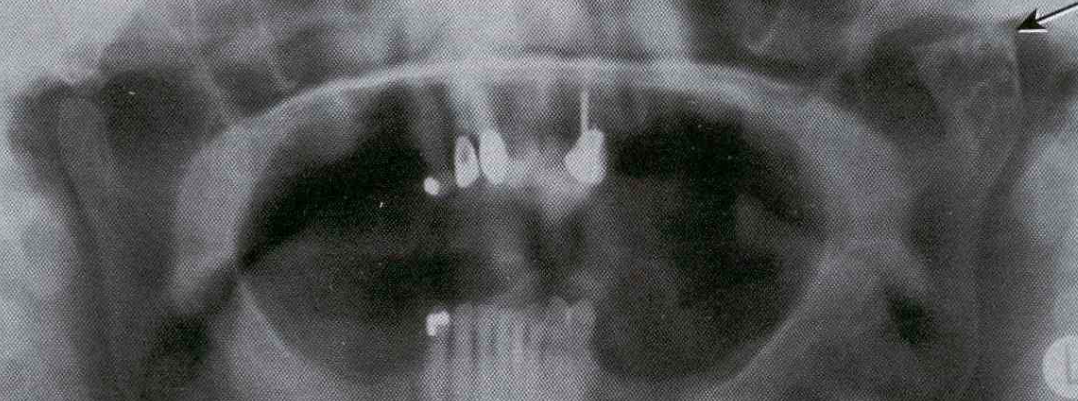

Eagle’s Syndrome (Or Stylohoid Syndrome and Carotid Artery Syndrome)